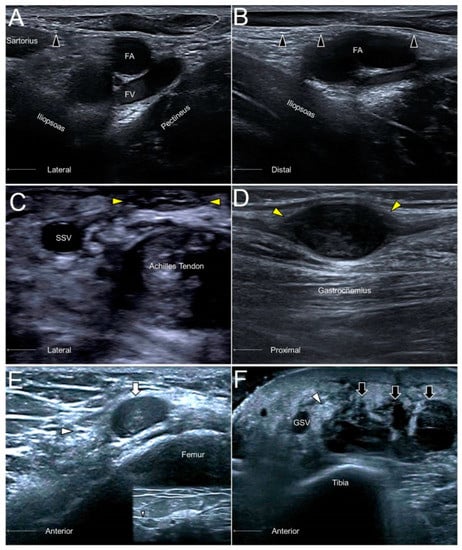

Like in most of the cutaneous nerves, an AFCN neuropathy commonly ensues due to iatrogenic injuries, e.g., a total knee replacement. Other causes comprise vein stripping, bypass grafting, lipoma excision, lymph node compression (Figure 10A,B), and abscess removal. US imaging may reveal segmental nerve swelling or, more severely, neuromas in symptomatic cases [28].

11.3. Clinical Implication

13.3. Clinical Implication

The sural nerve is in proximity to the small saphenous vein and can be injured during surgeries for varicose veins. Another cause of nerve injury would be related to Achilles tendon ruptures, whereby the nerve may be entrapped by an adjacent hematoma (Figure 10C). The nerve can also be traumatized by a foreign body due to its superficial lateral position at the distal segment. Neuromas are not rare sonographic findings in patients with suspicion of sural nerve neuropathies (Figure 10D) [34].

Figure 10. The short- (A) and long- (B) axes imaging of the anterior femoral cutaneous nerve (black arrowhead) compressed by an inguinal lymph node (dotted circle). A sural nerve (yellow arrowhead) neuroma in a male following Achilles tendon repair (C). A sural nerve schwannoma in a female with chronic calf pain (D). A swollen segment (white arrowhead) and a relatively normal portion (smaller white arrowhead) of the saphenous nerve adjacent to a hematoma (white arrow) of the distal femur (E). A thickened saphenous nerve (white arrowhead) next to serosanguinous fluid (black arrow) in a female with a degloving injury of the leg (F). FA, femoral artery; FV, femoral vein; SSV, small saphenous vein; great saphenous vein.